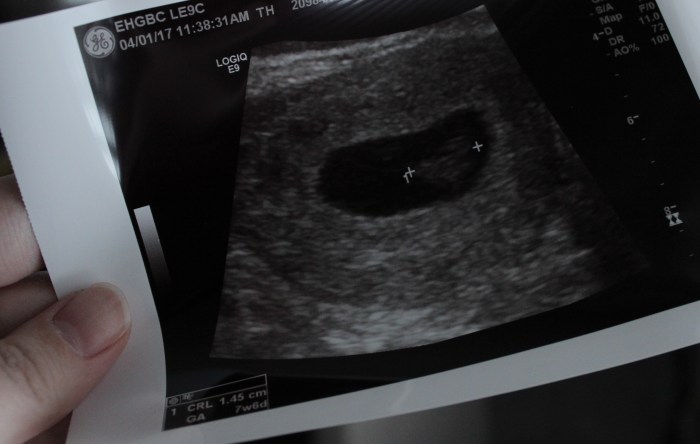

You are not a do-over or a second chance. I saw your precious face on that ultrasound and whatever name we decide fits you, I promise that Mulligan isn’t it.